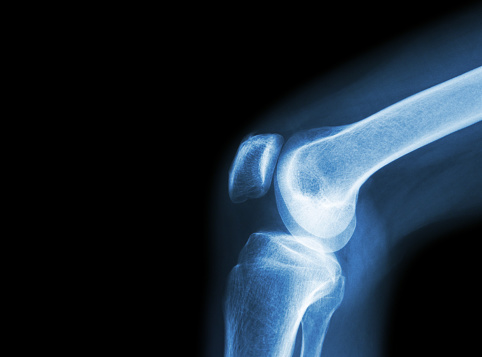

3D printing could provide treatment to osteoarthritis patients in the near future